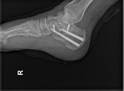

微创空心钉治疗术后X片

目前国际上跟骨骨折微创治疗的方法主要有:1,经皮撬拨复位内固定技术;2,小切口切开复位内固定技术;3,关节镜辅助下的跟骨骨折切开复位技术;4,跟骨髓内钉技术;5,3D打印辅助治疗技术;6,球囊扩张复位成形技术;7,外固定支架固定技术。其中经皮撬拨复位内固定技术是最早应用于跟骨骨折的微创治疗方法,也是所有跟骨微创治疗的基础。手术中术者利用特殊工具,在不做暴露骨折端的切口、不显露骨折部位的情况下,利用闭合复位的方法对跟骨进行复位,术者利用透视仪器监测及评估复位效果。如复位满意,即可在复位状态下置入克氏针临时固定,再利用螺钉完成最终的固定。微创空心钉治疗技术能以极其微小的创伤完成跟骨骨折的复位和固定,与传统切开复位钢板内固定术相比,微创空心钉治疗技术具有创伤小、有利于早期加速康复及减少医疗费用等优势。而且,由于跟骨骨折后局部常会出现不同程度的肿胀,传统的治疗方式常需要在等待较长的时间以待肿胀的消退,才能进行切开复位内固定手术,否则软组织的并发症会明显增加。这样,既浪费医疗资源,也会增加患者不必要的经济负担。有研究显示,应用微创空心钉治疗跟骨骨折可以获得不低于甚至优于切开复位钢板内固定术的疗效。对于软组织条件较差(如严重张力性水疱、皮肤存在创面、局部骨块压迫所致局部皮肤条件不佳等)者,或者存在系统性疾病(如糖尿病控制不佳、长期吸烟等)预计伤口并发症发生率较高的患者,更应优先考虑采用此技术。